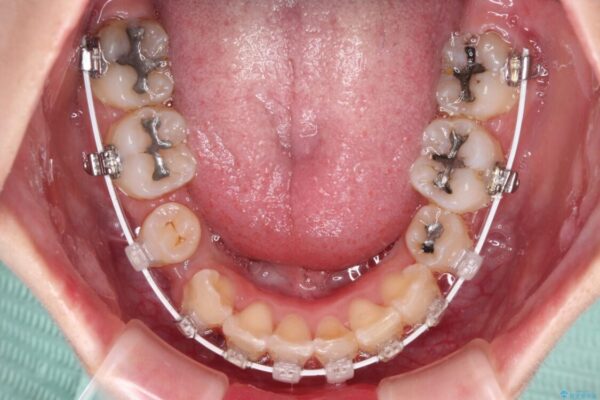

治療途中

• デコボコと深い咬み合わせ ワイヤー装置での抜歯矯正 治療途中画像

咬み合わせが深く、そのままでは上顎の抜歯スペースが閉じきらない可能性があったため、治療初期から深い咬み合わせを改善させるように試みました。

実際にはなかなか改善されず、当初予定よりも治療期間がやや長期化してしまいました。